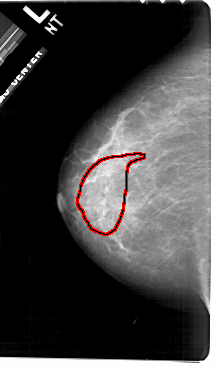

A_1906_1.RIGHT_CC

RIGHT_CC LINES 5476 PIXELS_PER_LINE 3166 BITS_PER_PIXEL 12 RESOLUTION 43.5 OVERLAY

FILE: A_1906_1.RIGHT_CC.OVERLAY

TOTAL_ABNORMALITIES 1

ABNORMALITY 1

LESION_TYPE MASS SHAPE ARCHITECTURAL_DISTORTION MARGINS SPICULATED

ASSESSMENT 5

SUBTLETY 4

PATHOLOGY MALIGNANT

TOTAL_OUTLINES 2

BOUNDARY

CORE